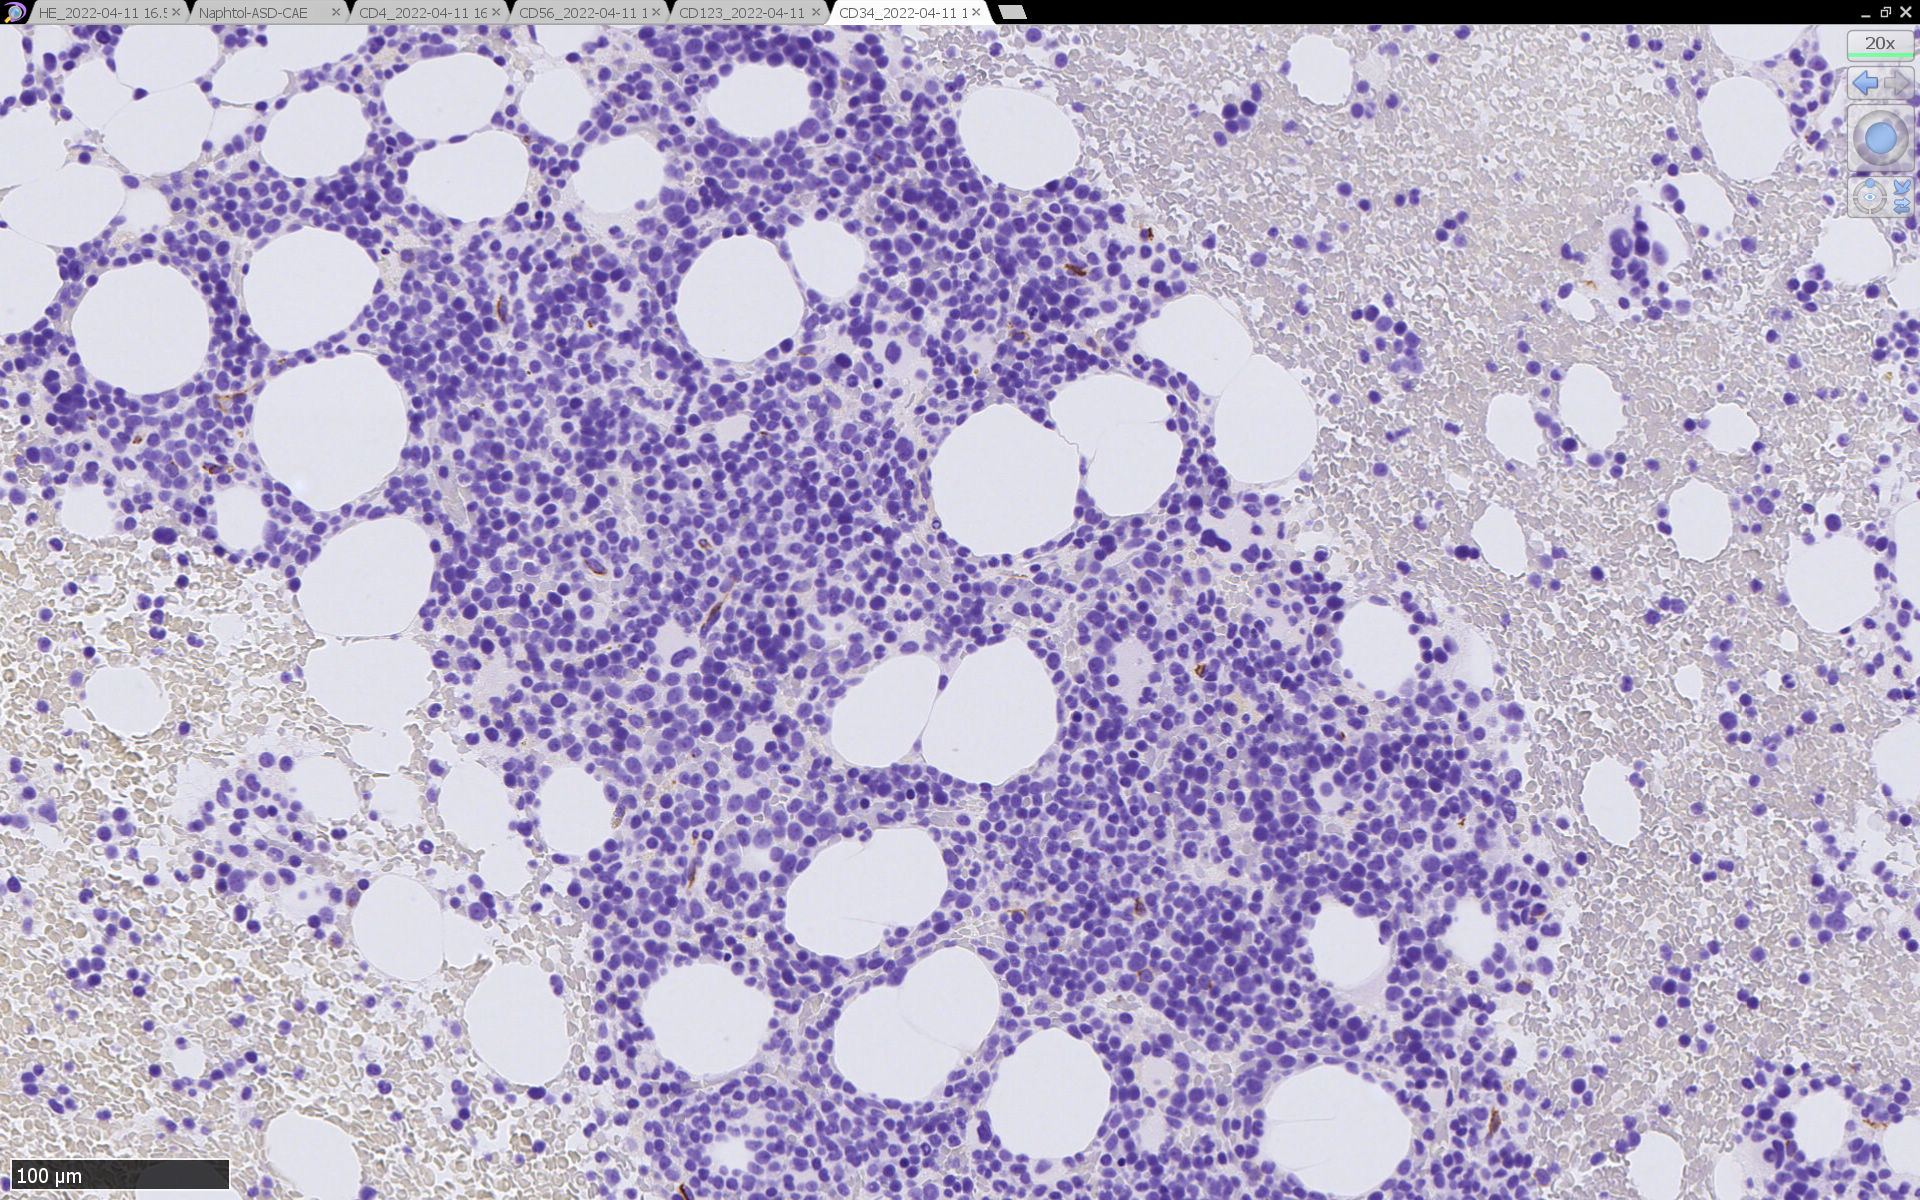

HEでは腫瘍細胞の同定が難しい. 本症例は ASD-Giemsa染色を見ても, 腫瘍胞巣はよくわからなかった. 皮膚が先に診断がつき, 次いでBone marrowだったため, 免疫染色にすすめたが, Bone marrowが先だと診断に困ったかもしれない.

免疫染色

CD4は染まりすぎの感がある(濃く染まる細胞はCD4+ T-cellかもしれない). CD56, CD123が陽性で可能性が高くなり, BPDCNの診断にはCD34は陰性であることが必要

TCF4、CD123、TCL1をconsultationにより染色していただき, 陽性を確認した. CD34-, lysozyme-, CD123(おいてある病院は少ないかも)をしらべて, BPDCN研究会あてconsultationをする流れでしょうか.